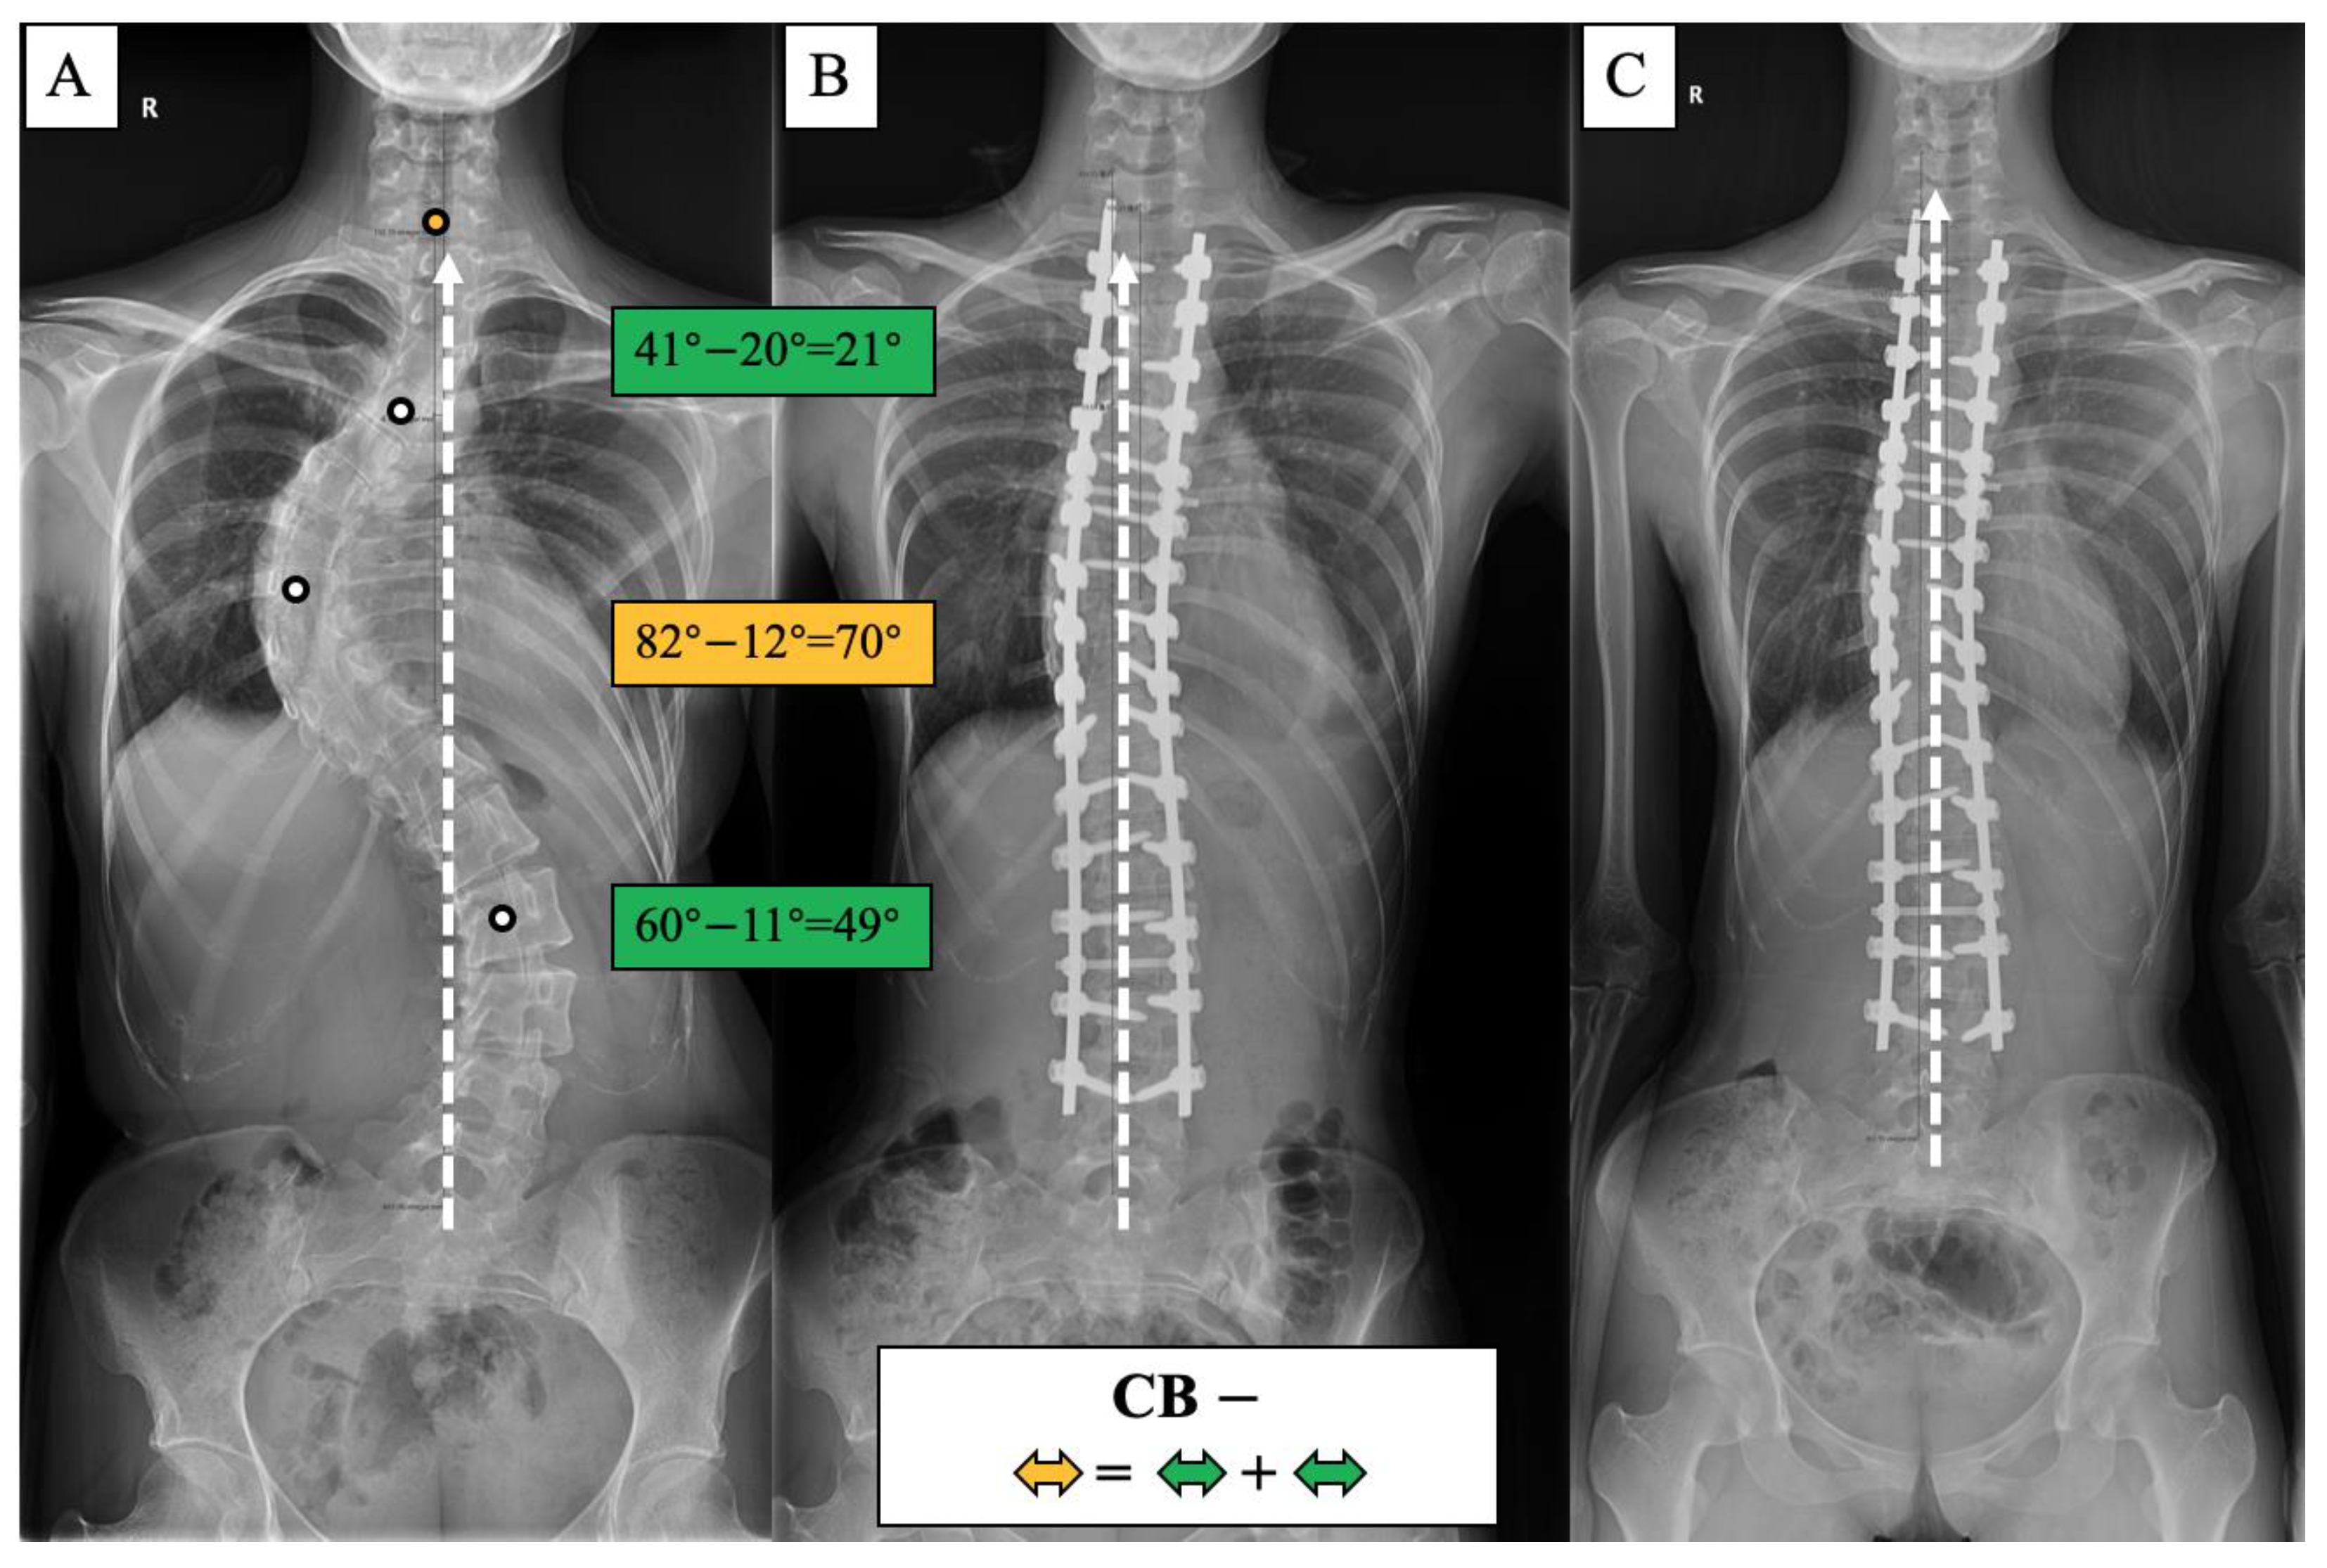

Figure 5.

CB− case, 23-year-old female AdIS patient ((A): preoperation, (B): postoperation, and (C): 2-year follow-up). The main thoracic curve was corrected from 82° to 12° (70° correction). The upper thoracic curve was corrected from 41° to 20° (21° correction), and the thoracolumbar curve was corrected from 60° to 11° (49° correction). The correction rate of the main curve matched the compensatory curves, and the coronal plane balance was maintained after surgery and long-term follow-up.